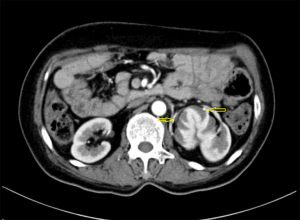

A 45-year-old woman was admitted to hospital complaining of a 1-month history of dizziness, and a transient ischemic attack was diagnosed. During a lung examination, her left kidney was found to be abnormal. The patient was not known to have kidney abnormalities, and there was no genetic history of this condition in her family. The patient did not present clinical symptoms of low back pain, hematuria, or urinary tract infection, and laboratory tests of renal function and urine routine were within normal ranges. The patient had no history of hypertension. A CT plain scan showed abnormalities in the left renal artery, vein, and ureter, and a reversed renal parenchyma with the collecting system protruding, while the right kidney was completely normal. Enhanced CT suggested that there was an artery in the left kidney, which entered the renal parenchyma in a mesh shape. There were 2 primary thick branches of deep veins, which merged with the reproductive vein at the renal pedicle and then merged into the inferior vena cava. The renal parenchyma was in a state of eversion and folding, and the renal papilla was prominent. Each renal papilla corresponded to a renal calyx, which converged into the renal pelvis on the ventral side (Figures 1,2). Using a software application (Mimics Innovation Suite 19.0, Materialise, Leuven, Belgium), we created a 3D reconstruction of the patient’s kidneys. The 3D-reconstructed images (Figures 3,4) showed that the right kidney was normal in anatomy and that the left kidney was abnormal. In Figures 3,4, it can be seen more intuitively and clearly that the left kidney has poor rotation, irregular physical contours, and an uneven surface; the renal pelvis and ureter are distributed in a “Y” shape. The final clinical diagnosis was CAKUT, and the patient’s clinical symptoms disappeared after conservative treatment. As the patient had no urinary system discomfort and her physical and laboratory examinations were normal, we prescribed a dynamic observation treatment plan with annual renal function and urinary system USs.